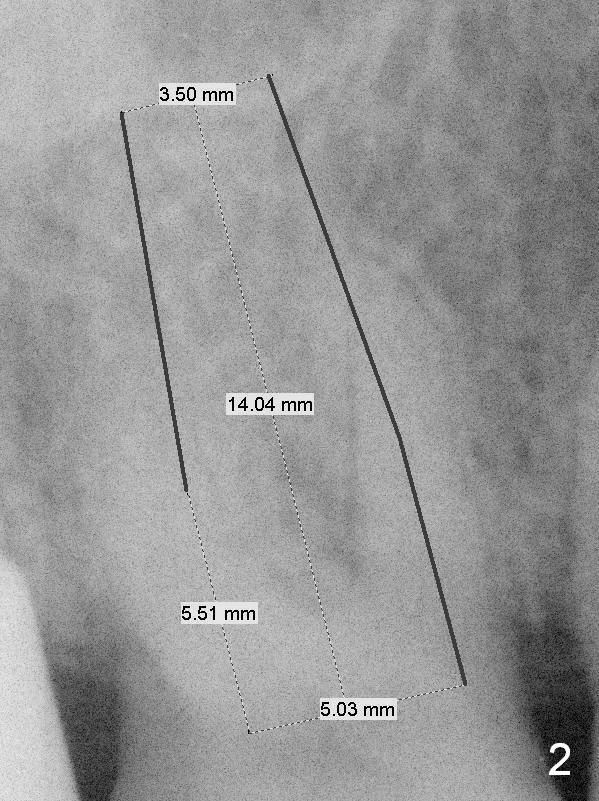

Provisional to Support Buccal Gingiva A 67-year-old woman with Parkinson disease has sign of several tooth chip. The tooth #3 fractures mesiodistally 1 year 7 months post cementation of the crown at #2. Take photos to show the crack line. After extraction (Metronidazole), explore the socket to determine bone integrity. If the septal crest is wide, use 1.6 drill (take 1st PA PRN) and Marking Bur before 4.3 mm Magic Drill. Otherwise use sequential drills, or alternating with Magic Expander if the bone is soft. No matter whether IBS (Fig.1) or Tatum (Fig.2) implant is placed, an immediate provisional will be fabricated so that the margin of the provisional is subgingival to prevent buccal plate collapse and bone graft leakage. Return to